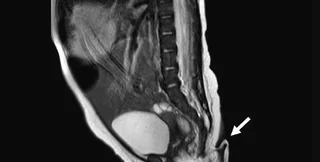

Медики на чолі з доктором Хосуе Руеда вважають, що дитина стала першою дитиною, що народилася з хвостом, у Мексиці. Крихітка з'явилася на світ у лікарні в Нуево-Леоні в результаті кесаревого розтину. Батьки дівчинки були здорові, проте медики швидко помітили 5,7-сантиметровий хвіст, який був м'яким із загостреним кінчиком, покритим шкірою та тонкими волосками.

У діаметрі "хвіст" був лише від 3 до 5 мм

Медики зазначають, що в діаметрі "хвіст" був лише від 3 до 5 мм, був покритий шкірою та тонкими волосками. Цікаво, що лікарі могли пасивно рухати "хвіст", не викликаючи у дівчинки болю, проте мимовільних рухів відростка не спостерігалося. Крім того, медики провели тест на реакцію, "вколовши" відросток голкою, в цей момент новонароджена заплакала.